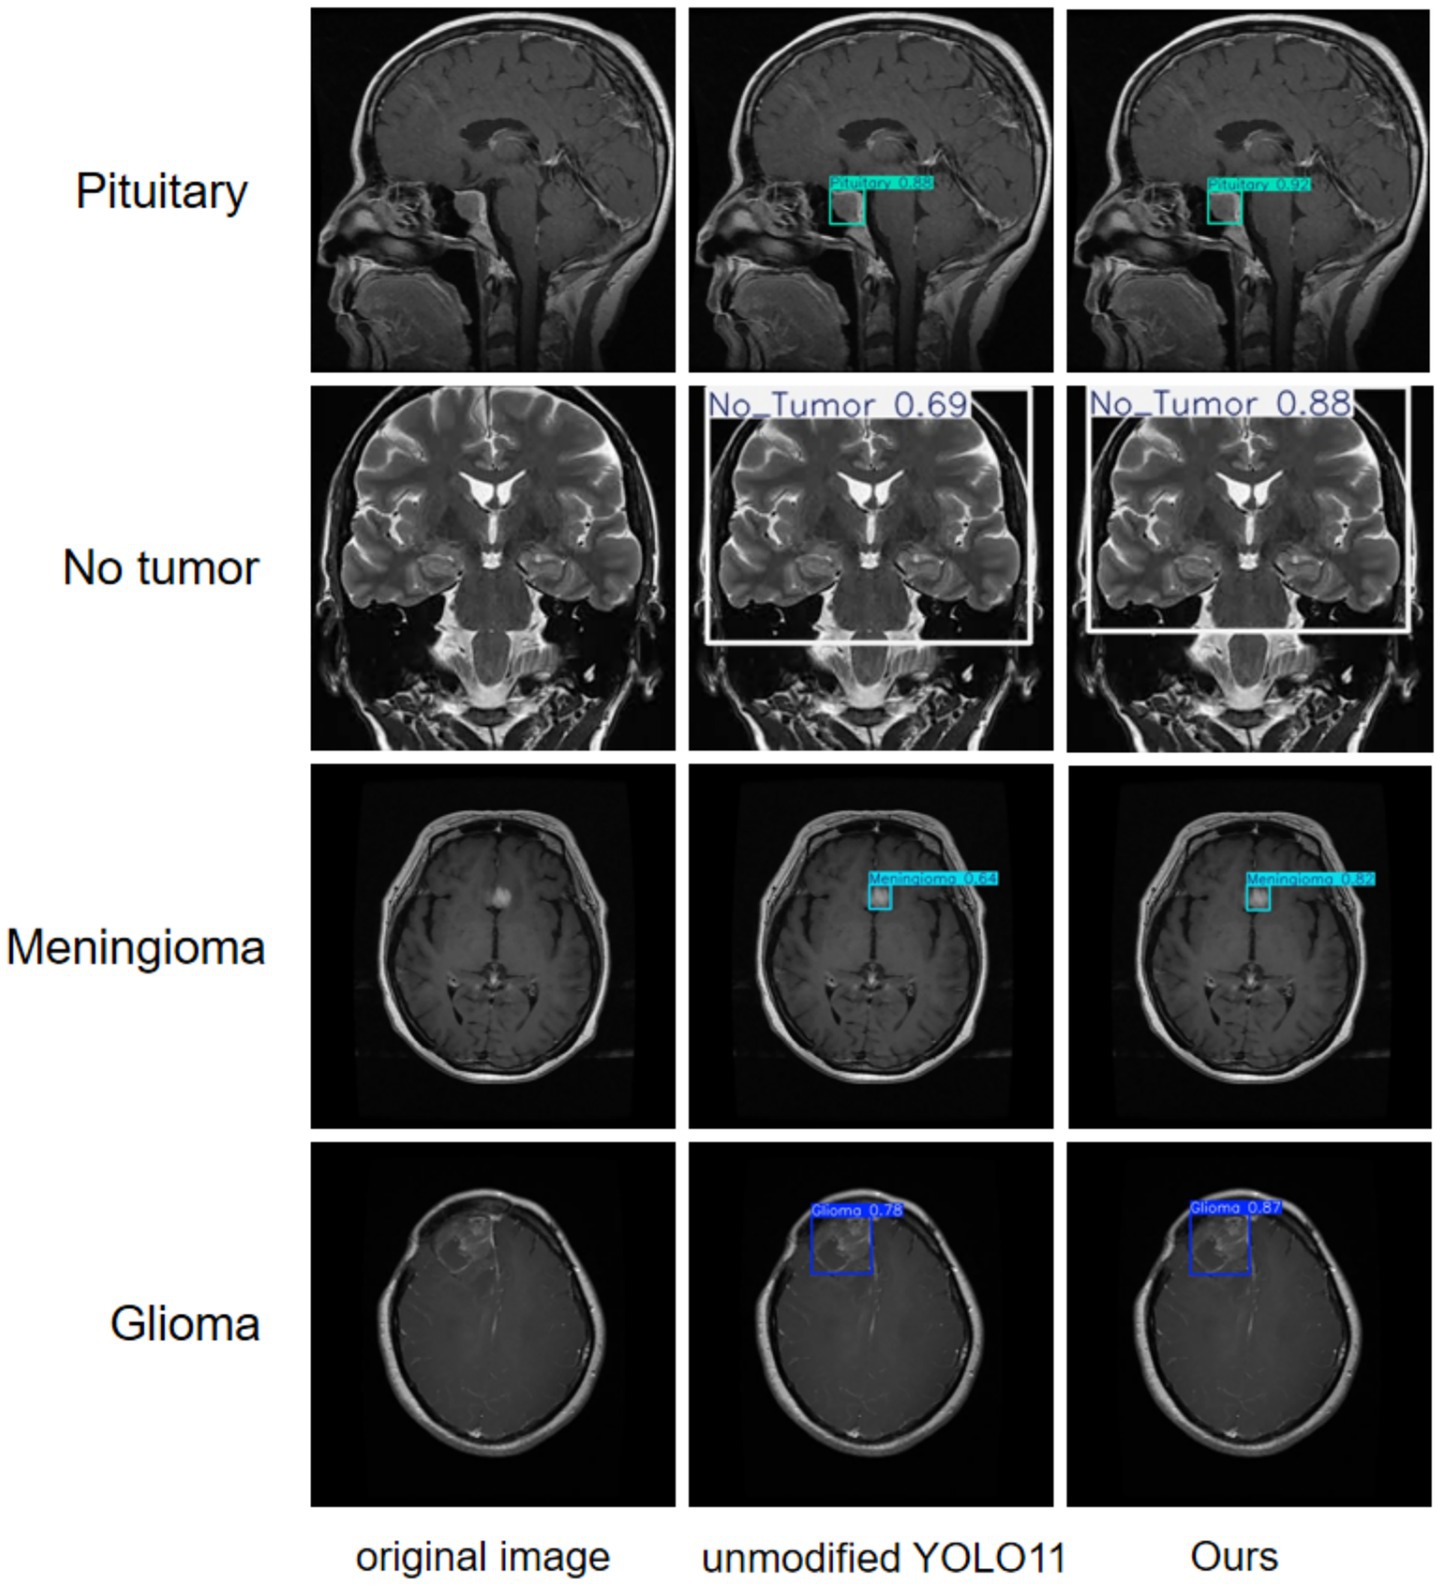

A more intuitive view of the effects before and after the improvement can be seen in the original and detection result plots randomly selected from the internal and external test sets, see Figures 13, 14. Each line compares the effects of a brain tumor type before and after detection and before and after the model improvement, with the original plot, the original YOLO11n detection result plot, and the improved YOLO11n detection result plot, in order from left to right. The text on the left side above the target box in the detection result plots is the brain tumor type, and the number on the right side is the detection confidence level. Column 3 of both Figures 13, 14 show that the improved model can detect gliomas, meningiomas, pituitary tumors, and no tumors (entire brain region) with high confidence. Table 5 shows the quantitative results of the detection performance for various categories of the improved model in the external test set.

Figure 14. Classification detection results of YOLO model before and after improvement on external test set.